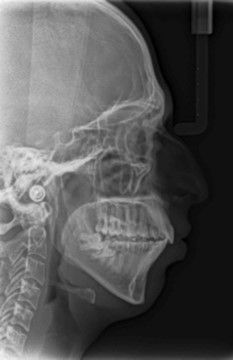

Cephalometric analysis revealed a skeletal Class II pattern, with an orthognathic maxilla and retrognathic mandible with high mandibular plane angle and severely proclined maxillary and mandibular incisors with increased lower anterior facial height. (Figure 3).

Post treatment lateral cephalometric radiograph was taken to assess the treatment changes. (Figure 9). The changes in maxilla in the anteroposterior direction was insignificant, however an increase in the length of the mandible measured from Condylion (Co) to Gnathion (Gn) and an increase in anterior facial height was observed. Maxillary incisors were retracted dramatically by 8mm and the mandibular incisors were proclined by 3mm to camouflage the skeletal class II malocclusion.(Table 1). Effective expansion of the maxillary constriction as an end-of treatment goal was achieved. (Figure 10a,Figure 10b).

| Variable | Norm | Pre-treatment | Post-treatment |

| SNA (degrees) | 82 ± 2 | 80 | 80 |

| SNB (degrees) | 80 ± 2 | 72.5 | 71 |

| ANB | 2 ± 2 | 7.5 | 9 |

| U1 to NA (degrees) | 22 | 26 | 17 |

| U1 to NA (mm) | 4 | 9 | 1 |

| L1 to NB (degrees) | 25 | 30 | 33 |

| L1 to NB (mm) | 4 | 8 | 11 |

| N-Me (mm) | 123 ± 5 | 112 | 142 |

| N-ANS (mm) | 56 ± 3 | 53 | 66 |

| ANS-Me (mm) | 70 ± 3 | 59 | 78 |

| FMA (degrees) | 25 | 32 | 36 |

| Co-Gn (mm) | - | 102 | 121 |

| E-plane LL (mm) | -2 ± 2 | 2.5 | 5 |